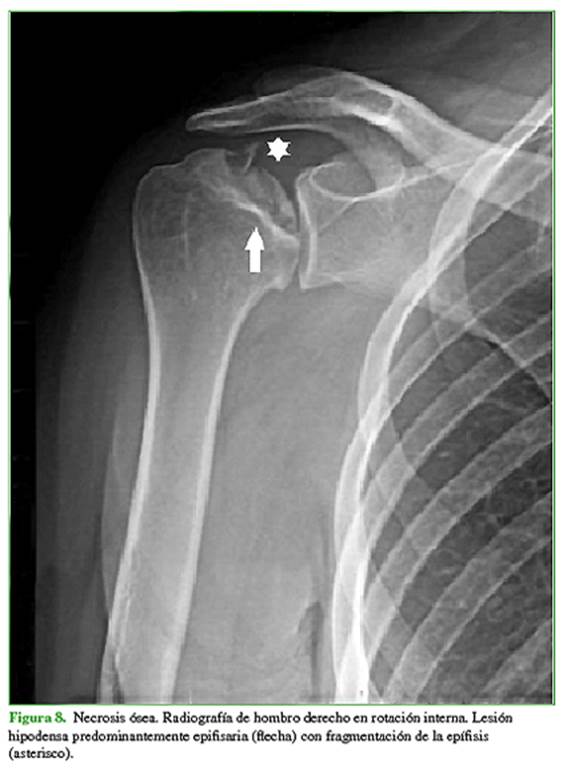

Los diagnósticos diferenciales más frecuentes son focos de hiperplasia de médula ósea grasa, displasia fibrosa (Figura 5), quiste óseo simple o aneurismático (Figura 6), lesiones condrales (encondroma, condrosarcoma) (Figura 7), infarto óseo antiguo, necrosis avascular (Figura 8) y fibroma condromixoide (Figura 9).